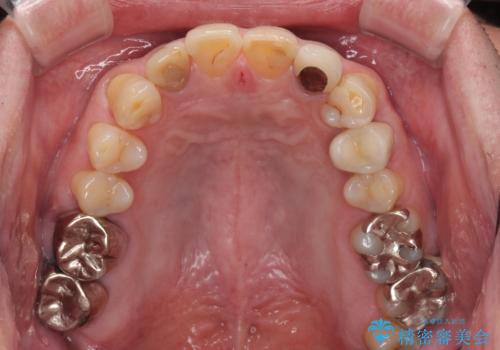

- 前歯の色味が気になるとのことで来院された患者様です。左上の2番目の歯の歯茎のラインと被せものの境目の適合が悪い状態だったのでオールセラミッククラウンによる補綴治療を行っていくことになりました。

金属の土台を外し、ファイバーコアを築造し、オールセラミッククラウンに適切な形に整えました。

左上の2番目の歯の型どりの段階で患者様より右上の2番目の歯も治療をしてほしいとのことで、根管治療(保険診療)、ファイバーコア、オールセラミッククラウンによる補綴治療を行いました。

歯と歯茎の間に圧排糸と言われる糸を入れてシリコーン印象材にて型どりをしました。